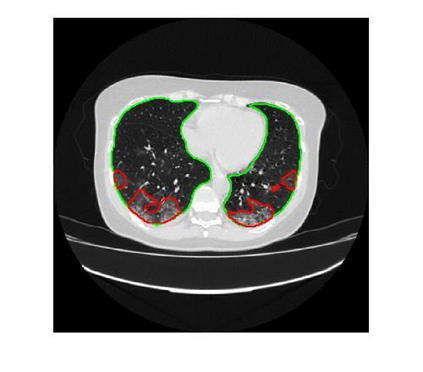

Since the breakout of coronavirus disease (COVID-19), the computer-aided diagnosis has become a necessity to prevent the spread of the virus. Detecting COVID-19 at an early stage is essential to reduce the mortality risk of the patients. In this study, a cascaded system is proposed to segment the lung, detect, localize, and quantify COVID-19 infections from computed tomography (CT) images Furthermore, the system classifies the severity of COVID-19 as mild, moderate, severe, or critical based on the percentage of infected lungs. An extensive set of experiments were performed using state-of-the-art deep Encoder-Decoder Convolutional Neural Networks (ED-CNNs), UNet, and Feature Pyramid Network (FPN), with different backbone (encoder) structures using the variants of DenseNet and ResNet. The conducted experiments showed the best performance for lung region segmentation with Dice Similarity Coefficient (DSC) of 97.19% and Intersection over Union (IoU) of 95.10% using U-Net model with the DenseNet 161 encoder. Furthermore, the proposed system achieved an elegant performance for COVID-19 infection segmentation with a DSC of 94.13% and IoU of 91.85% using the FPN model with the DenseNet201 encoder. The achieved performance is significantly superior to previous methods for COVID-19 lesion localization. Besides, the proposed system can reliably localize infection of various shapes and sizes, especially small infection regions, which are rarely considered in recent studies. Moreover, the proposed system achieved high COVID-19 detection performance with 99.64% sensitivity and 98.72% specificity. Finally, the system was able to discriminate between different severity levels of COVID-19 infection over a dataset of 1,110 subjects with sensitivity values of 98.3%, 71.2%, 77.8%, and 100% for mild, moderate, severe, and critical infections, respectively.